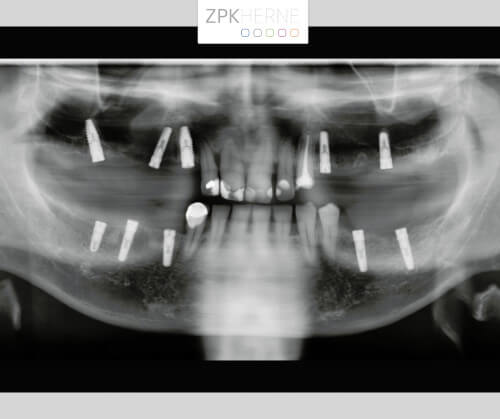

Nach der gründlichen Anamnese werden aktuelle 3D-Aufnahmen der Gebisssituation erstellt. Dabei kommt das Team um Herrn Dr. Mintert zu den folgenden Ergebnissen und Handlungsschritten:

Zur Vorbereitung auf den Tag der Operation wird eine Bohrschablone auf Basis der DVT-Planung angefertigt. So werden die genauen Positionen der einzelnen OP-Schritte festgehalten, damit keine Nervverletzung entsteht. Der chirurgische Eingriff findet unter Vollnarkose statt, hier ist genaueste Konzentration gefragt. Zunächst wird das OP-Gebiet gründlich gereinigt, damit keine Bakterien in die Wunde gelangen. Nun Schnittführung auf den Kieferkämmen: Das Gewebe wird vorsichtig abgelöst und der Knochen freigelegt. Die Bohrschablone wird anprobiert und die Bohrungen für die Implantate Schritt für Schritt durchgeführt. Die Implantate werden nach und nach maschinell eingebracht und radiologisch kontrolliert. Währenddessen wird eine mit Blutplättchen und Wachstumsfaktoren angereicherte Fibrinmembran (LPRF) hergestellt, indem eine gewisse Menge Blut des Patienten zentrifugiert wird. Dies dient der besseren Wundheilung und ist unter dem Begriff „Eigenbluttherapie“ als besonders schonende und effiziente Behandlungsmethode bekannt.

Die radiologische Kontrolle findet nach drei Monaten statt. Wie diese genau abläuft, haben wir in unserem Patientenfall zum Thema Lückenschluss im Unterkiefer genauer erklärt.